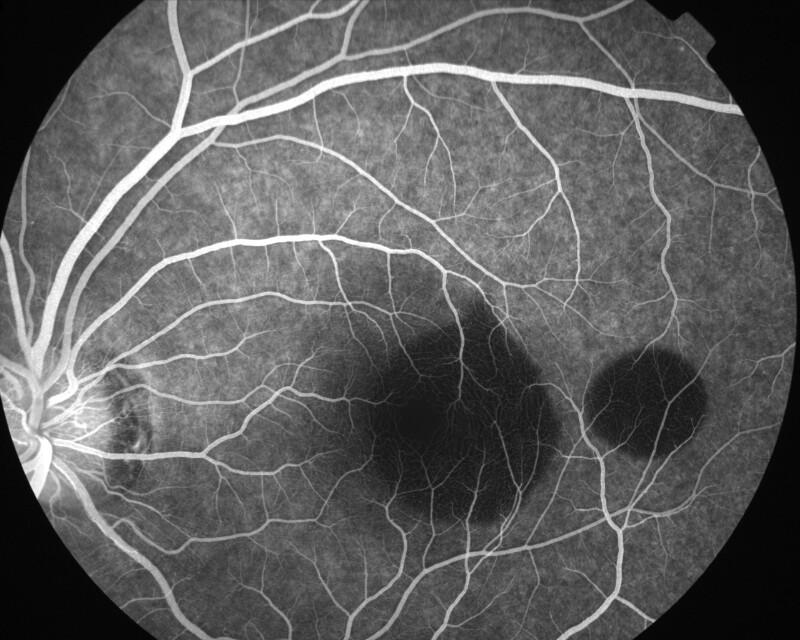

IMG0018.jpg